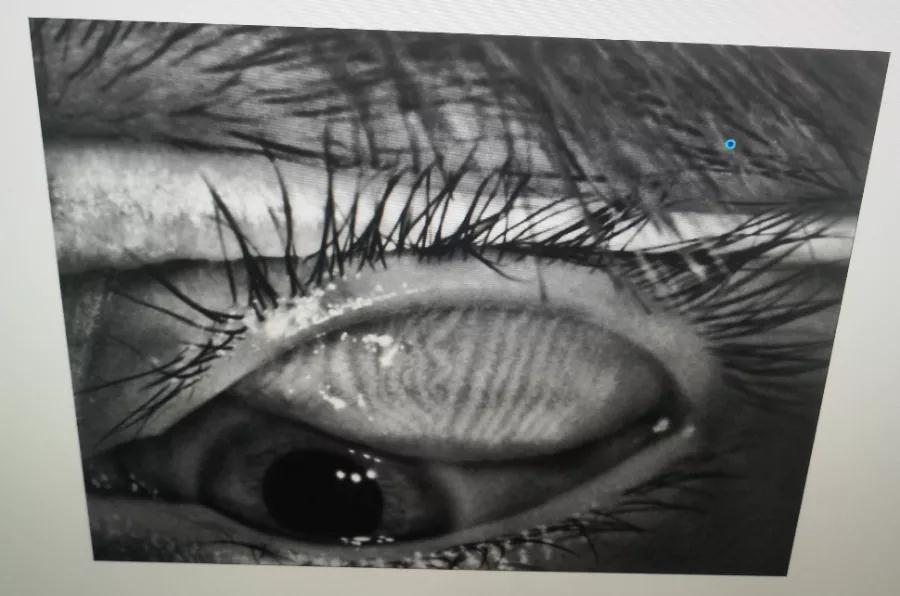

瞼板腺是排列在我們上下眼皮里面,分泌油脂的腺體,這些油脂是組成淚液的重要成分,可以讓淚水更長(zhǎng)時(shí)間的停留在眼球表面。瞼板腺油脂減少,淚水蒸發(fā)就會(huì)加快,眼球暴露在外的時(shí)間變長(zhǎng),會(huì)加重眼睛干澀,時(shí)間一久,干眼也就隨之而來(lái)。

通過(guò)熱敷并按摩擠壓上下眼瞼,將瞼板腺內(nèi)不能自行排出的分泌物推出,疏通堵塞的瞼板腺開(kāi)口。

熱敷可以促進(jìn)眼周部位的血液循環(huán),瞼板腺按摩能有效改善瞼板腺功能,解決絕大多數(shù)干眼患者油脂分泌不足問(wèn)題。

通過(guò)強(qiáng)脈沖光高溫消除蠕形螨蟲(chóng),同時(shí)脈沖光產(chǎn)生的熱量可以熔解軟化瞼酯,改善瞼板腺內(nèi)脂質(zhì)分泌物的流動(dòng)性,疏通瞼板腺,提高淚膜的穩(wěn)定性,恢復(fù)正常眼表功能和眼部“鎖水”能力,從病因上治療干眼。